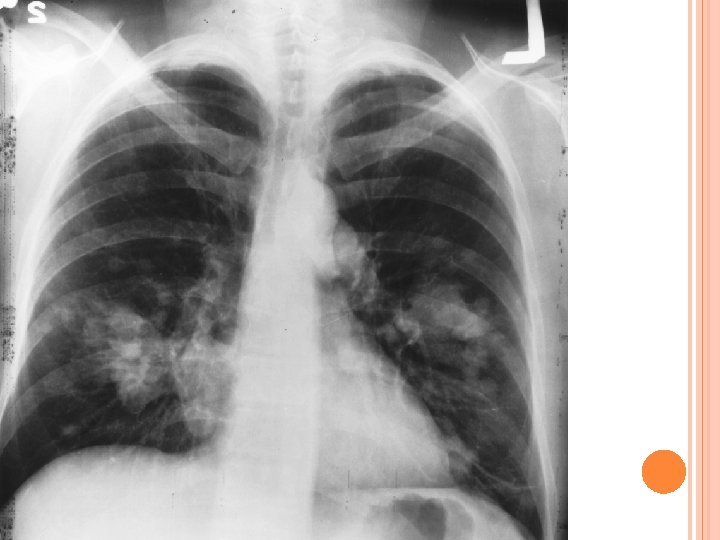

Pacientul, în vârstă de 40 de ani, fumător, se prezintă la Urgenţă pentru discomfort toracic şi o stare de slăbiciune generalizată. Cu ceva timp în urmă a remarcat o formaţiune la nivelul peretului toracic stâng care a crescut în dimensiuni în ultimele 3 luni. Recent a apărut parestezie la nivelul pielii care acoperă masa tumorală, pacientul menţionând faptul că a scăzut şi gradul de mobilizare al umărului său stâng.

Bărbatul este cunoscut ca fiind alcoolic, are o dentiţie precară şi acuză apariţia frecventă a unor abcese dentare, utimul din acesta apărând cu 2 luni în urmă şi remitându-se spontan. În ultimul an el reclamă o tuse seacă, neproductivă, însotită noaptea de transpiraţii. De asemenea, pacientul a pierdut în greutate în ultimele 4 săptamani. Între antecedentele sale ar mai fi de menŢionat o bronşită astmatiforma în copilărie. La examenul fizic pacientul este afebril, cu semne vitale stabile. Formaţiunea toracica are aproximativ 6 cm, este localizată în jurul mamelonului stâng, este fermă, imobilă şi nedureroasă la palpare. Pielea adiacentă nu prezintă nici o modificare din punctul de vedere al aspectului. Examenul pulmonar nu relevă nimic patologic, asemenea celui cardiovascular.

formaţiune pleurală stânga

Extensia masei pleurale stangi la CT

Formatiune extinsa in parenchimul pulmonar, insotita de adenopatie

Radiografia toracelui anterior si cea laterala evidentiaza o formatiune opaca in plamanul stang, cu extindere pleurala, cu ingrosarea apicala a pleurei si o zona cicatriceala in lobul superior. La computer tomograf se poate vizualiza de asemenea aceasta formatiune si extinderea si dimensiunile ei (10. 8 X 4. 1 cm). Mai mult decat atat, se sesizeaza o ingrosare a periostului coastelor adiacente. RMN-ul cu contrast aduce in atentia medicilor adenopatia supraclaviculara stanga si subliniaza extinderea pana la nivelul pectoralului mare a formatiunii, respectiv in profunzimea parenchimului pulmonar. Diagnostic?